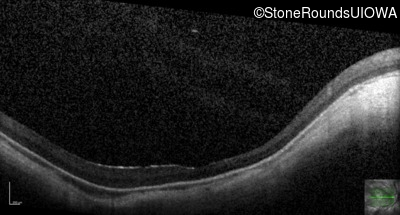

Optical Coherence Tomography - Right - 10/100 -2

Exemplar / OCT Stack